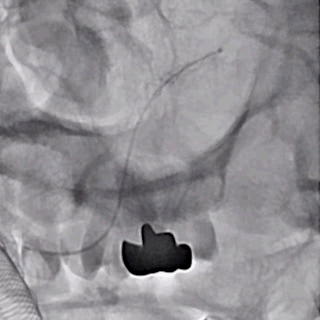

支架及支架微导管到位。

支架头端打开。

支架远端打开造影。

等张释放,支架中段打开至50%释放标记点。

支架中段打开造影。

支架近端打开,完全释放。

支架完全释放造影。

术后即刻造影。